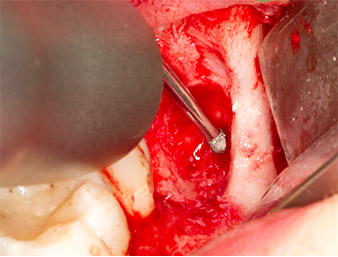

Using an instrument for periodontal debridement (Piezomed P1), the periodontal ligament space of the radix relicta was then widened minimally (Fig. 8).

The same activated instrument was inserted into the root canal and loosened the fragment as a result of its micro-oscillating vibrations (Fig. 9, 10).

Piezomed P1

Fig. 9: The Piezomed P1 instrument is recommended by the manufacturer primarily for periodontal debridement but is also suitable for surgical purposes. Here it is placed in the root canal after minimal widening of the periodontal ligament space.

Fig. 10: Due to its slender shape, the instrument can penetrate the root canal and remove the root remnant by means of micro-oscillation (vibration).